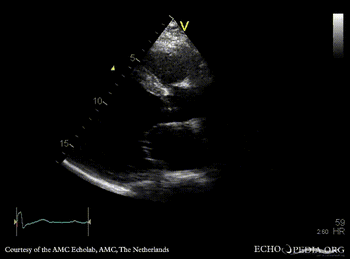

| Courtesy of: AMC Echolab, AMC, The Netherlands | |

| A2CH | A3CH |